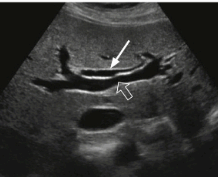

- 간외담관(extrahepatic bile duct)은 총 간관(CHD)과 총담관(CBD)으로 나뉘고 그 끝은 십이지장 내 유두부이다.

- 십이지장의 연동운동에 맞춰 유두 부네 담관의 개폐(open and close)를 확인한다.

- 간외담관에 대한 초음파검사는 유두부(vater's papilla)까지 묘출하는 것을 원칙으로 한다.

extrahepatic bile duct 3) 지방식 (fatty meal)